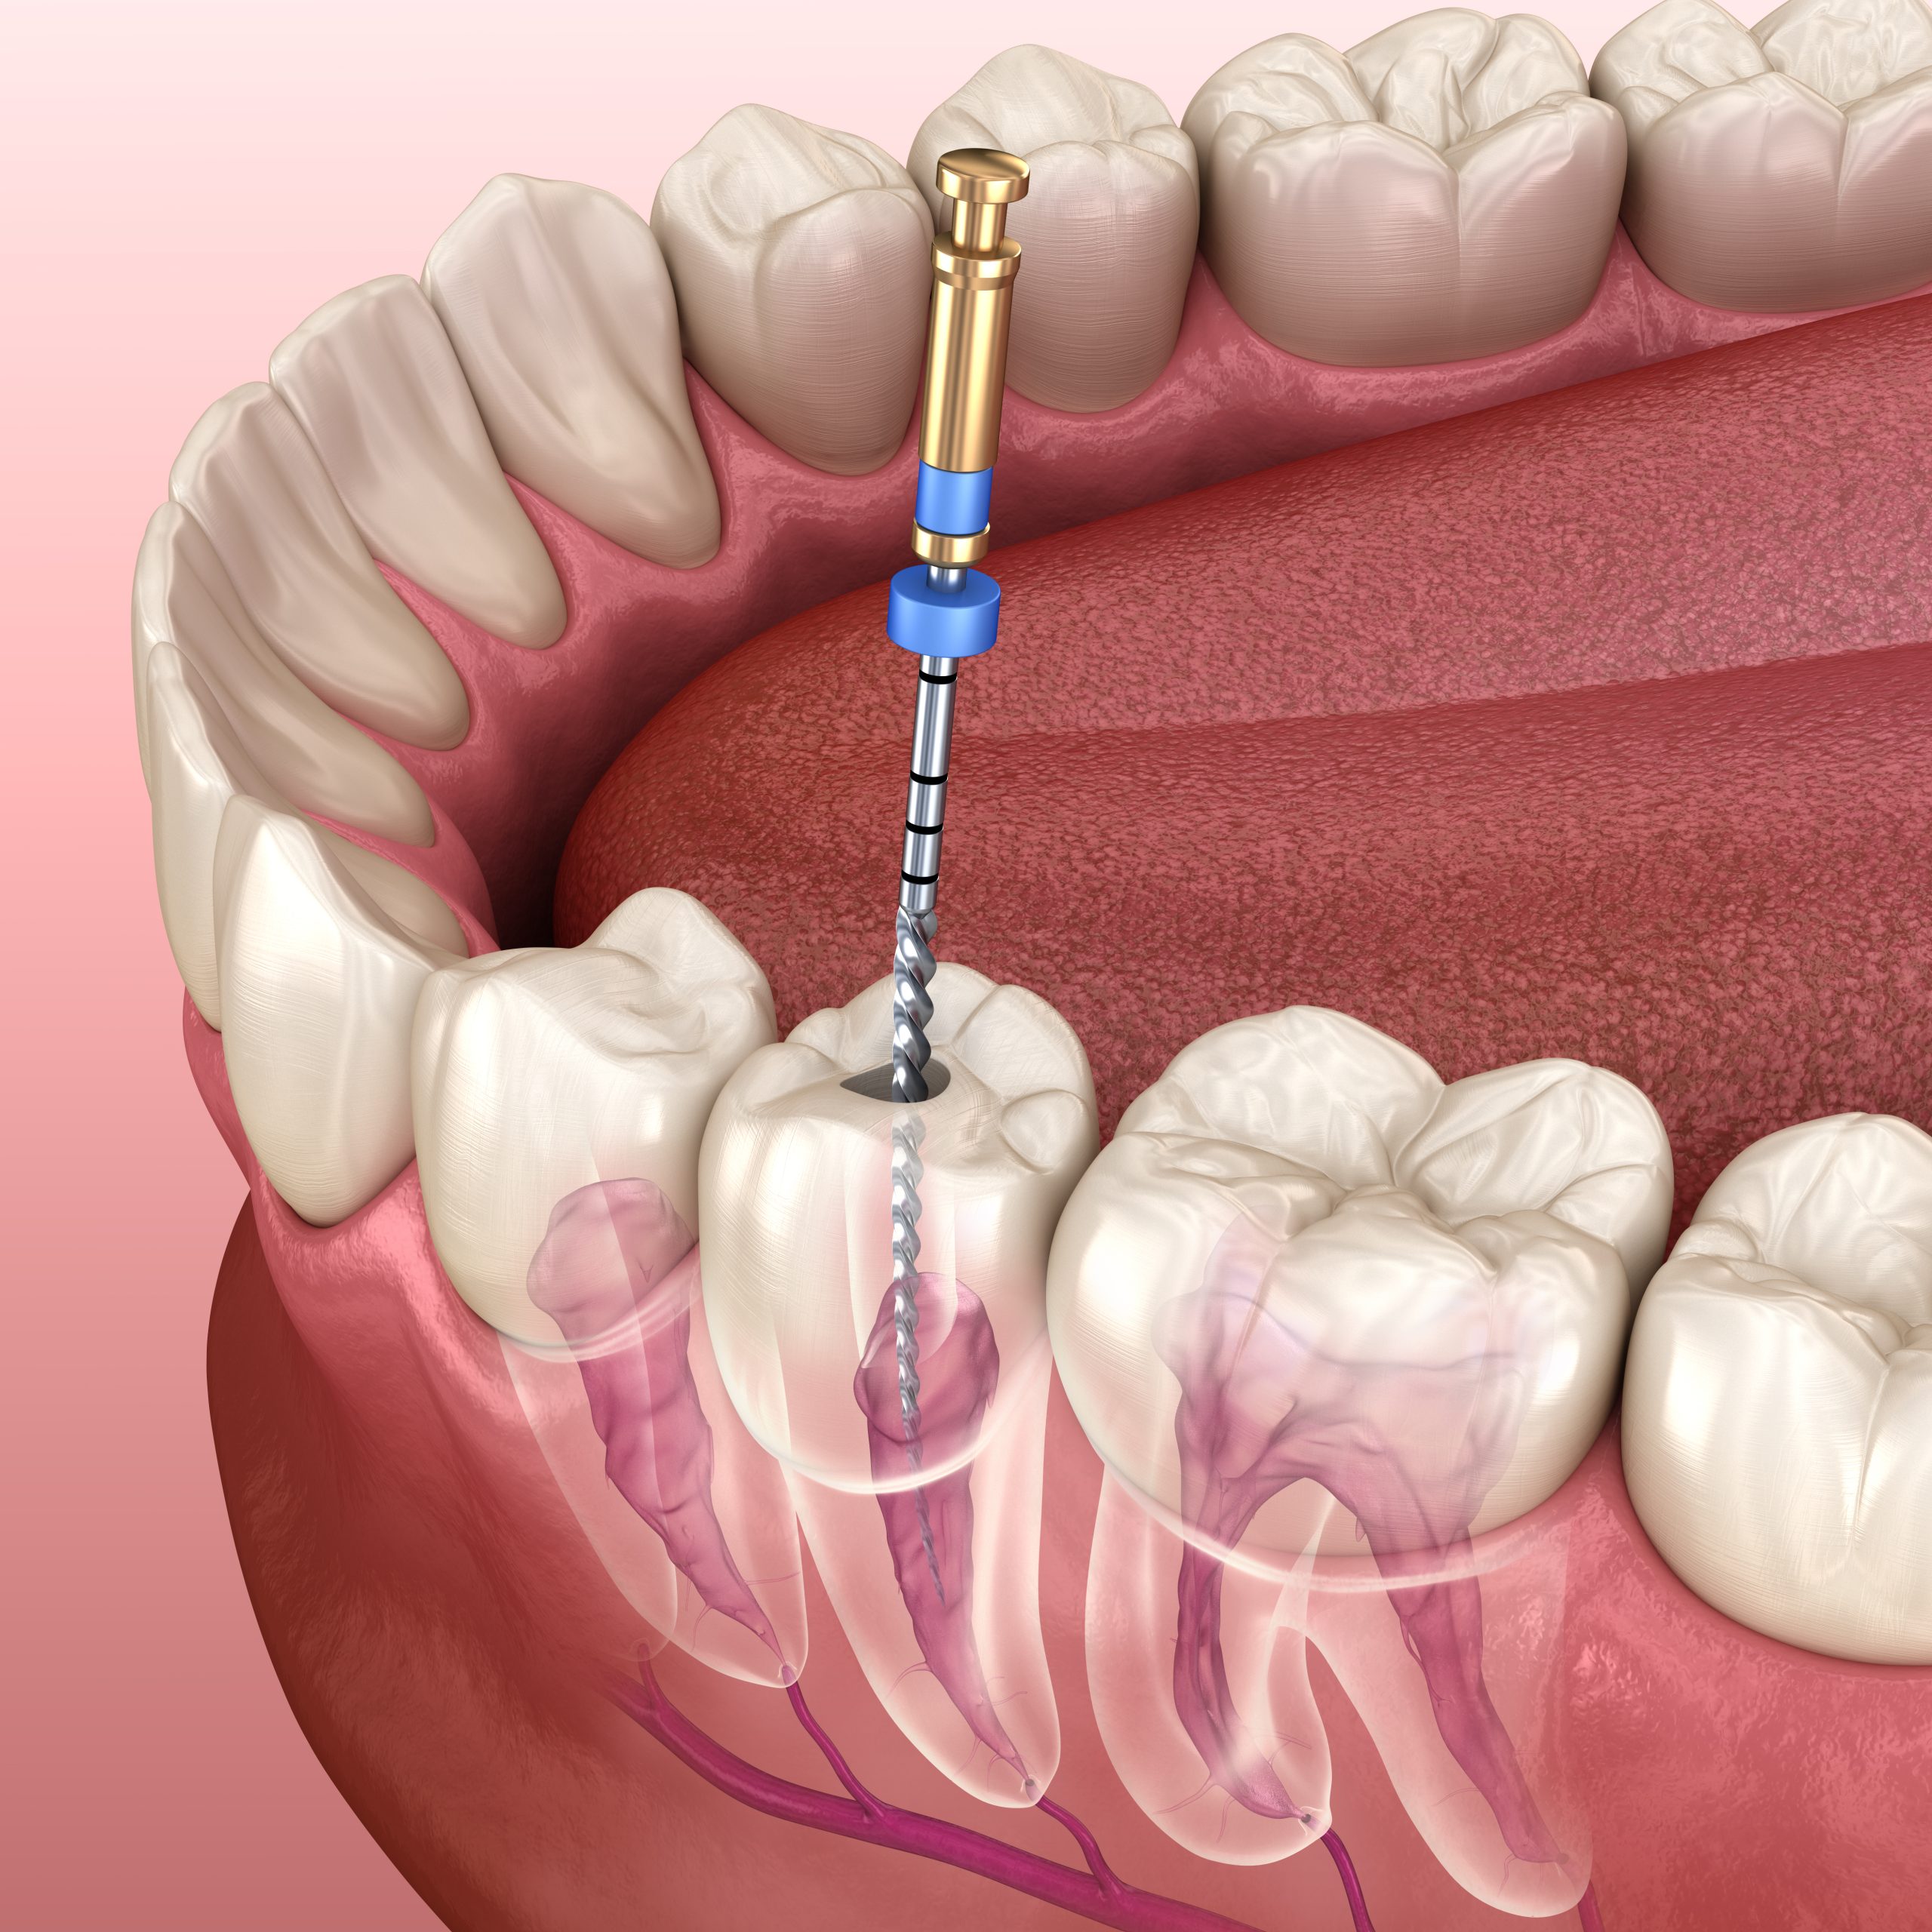

کلینیک دندانپزشکی دکتر علی نورافروز با محیطی آرام و کادری مجرب اماده خدمت رسانی و مشاوره به شما می باشد

با جدیدترین روش های روز دنیا

با جدیدترین روش ها و ابزار های دنیا سلامت دهان و دندان خود را به ما بسپارید